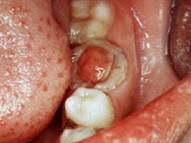

问题 慢性增生性牙髓炎的特点是息肉()

选项 A.充满整个龋洞 B.与牙髓相连 C.与牙龈相连 D.与牙周膜相连 E.与牙槽骨相连

答案 B